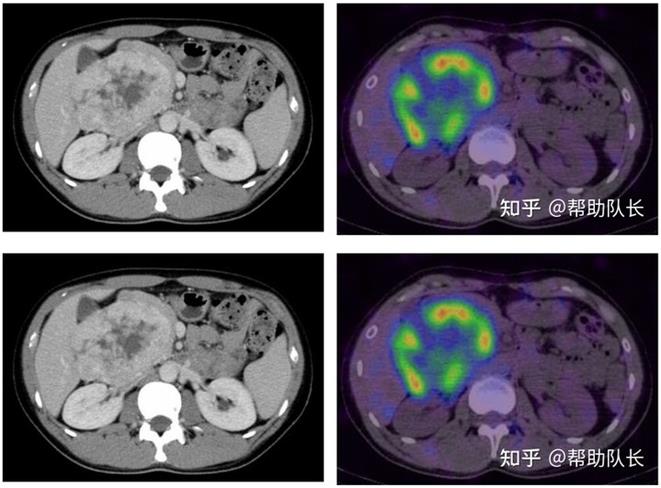

嗜鉻細胞瘤發生于腎上腺髓質的罕見腫瘤(良惡性均有)。約30~40%發生家族內遺傳,目前已經發現與SDHB?SDHD?VHL... -